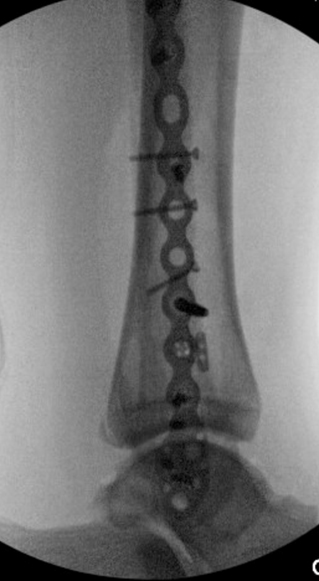

TOTAL ANKLE REPLACEMENT :: ORIF CALCANEUS :: ORIF ANKLE FRACTURE DISLOCATION :: COMPLEX BUNION AND LESSER TOE CORRECTION :: TALUS FRACTURE -1 :: TALUS FRACTURE -2 :: LISFRANC REPAIR :: COMPLEX TRIPLE ARTHRODESIS 1 :: COMPLEX TRIPLE ARTHRODESIS 2 :: MINIMALLY INVASIVE BUNION REPAIR 1 :: MINIMALLY INVASIVE BUNION REPAIR 2 :: ARTHROSCOPIC CARTILAGE REPAIR :: TENEX SPUR DEBRIDEMENT :: Haglunds Debridement and Achilles Repair